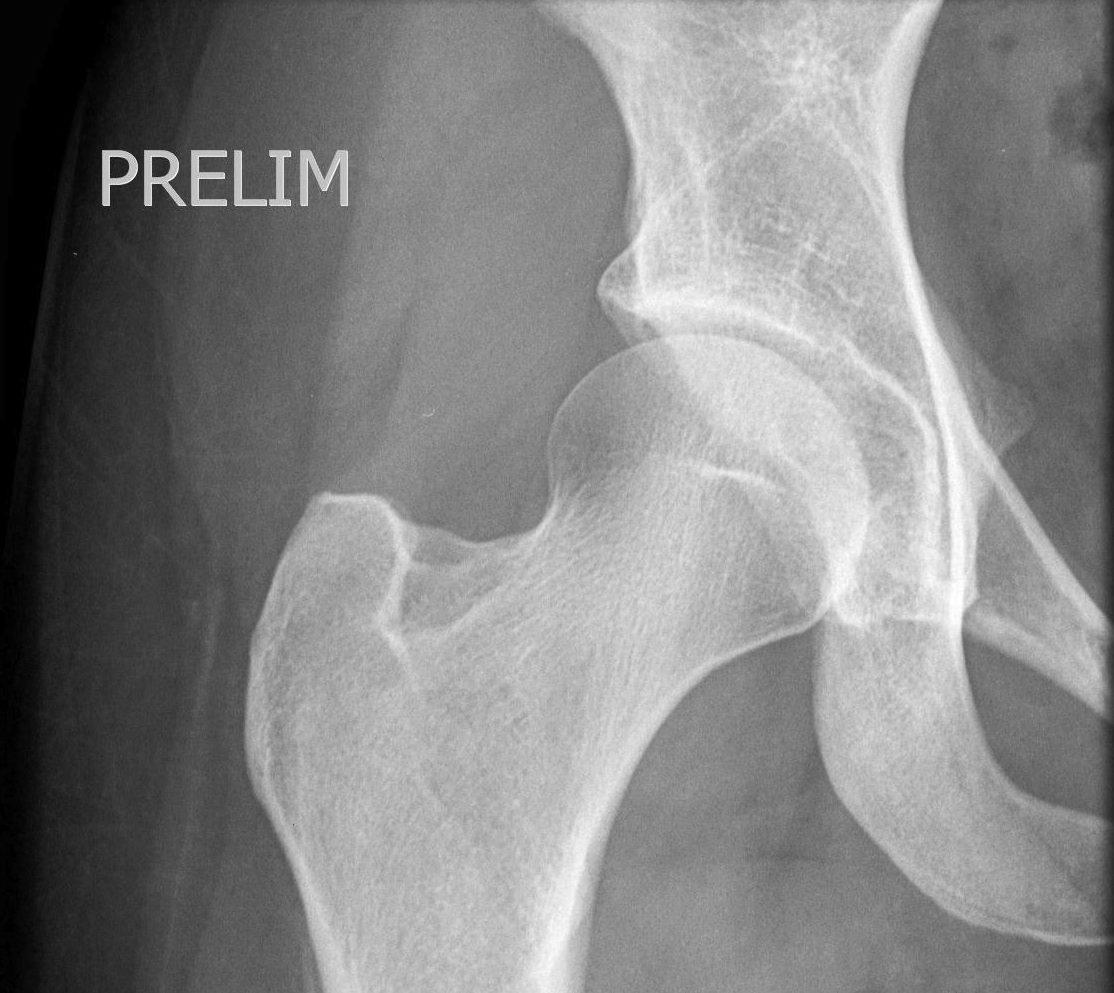

An MRI is very accurate at diagnosing a labral tear and any extra bone which may be contributing to the problem, such as a CAM (extra bone on the femoral side) or pincer (extra bone on the pelvis or acetabular side). Even more importantly, an MRI will look at the cartilage covering the femoral head (ball) and the acetabulum (socket). If you have significant cartilage damage, it is likely that a hip arthroscopy will not help. In this setting, injections of PRP or Hyaluronic acid may be used to treat your pain. Otherwise, a total hip replacement may be required.

During this keyhole procedure, anchors with sutures are used to repair the labral tear. Extra bone is taken away from the acetabulum and the femoral head / neck area as needed. Usually the hip capsule is opened to access the hip joint fully, and this is carefully closed at the end of surgery.